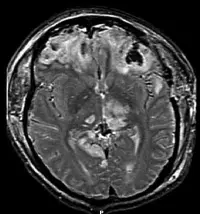

Symptoms of schizophrenia can be partly explained by disordered connectivity in the brain. It is already known that brains of schizophrenia patients are wired differently and work less efficiently. The scientists used a specific type of MRI that maps the wiring of the brain to identify how the brains of young people who have some symptoms of schizophrenia are wired differently.

They scanned 123 people who have vulnerability to psychosis, and 125 people without vulnerability and compared the differences in the wiring of their brains. The findings showed that in people who were vulnerable to schizophrenia, the ability of the brain network to transmit information from one region to another was reduced and some information pathways were rerouted. This affected certain  information hubs of the brain leading to widespread problems in information processing that is similar to schizophrenia.

Cardiff University’s Dr Mark Drakesmith, who led the research, said: “The changes we’ve identified in the brain networks are extremely subtle. However, using a specific type of Magnetic Resonance Imaging (MRI) which maps the wiring of the brain, we have made some key discoveries that would not have been detected using more established brain imaging techniques. The technique employs a branch of mathematics called ‘graph theory’, which allows us to examine complex architectural features of networks, such as efficiency of information transfer. This approach is traditionally used in computer science, but is now giving neuroscientists and psychiatrists new insights into how configurations of brain networks are altered in mental illness.“